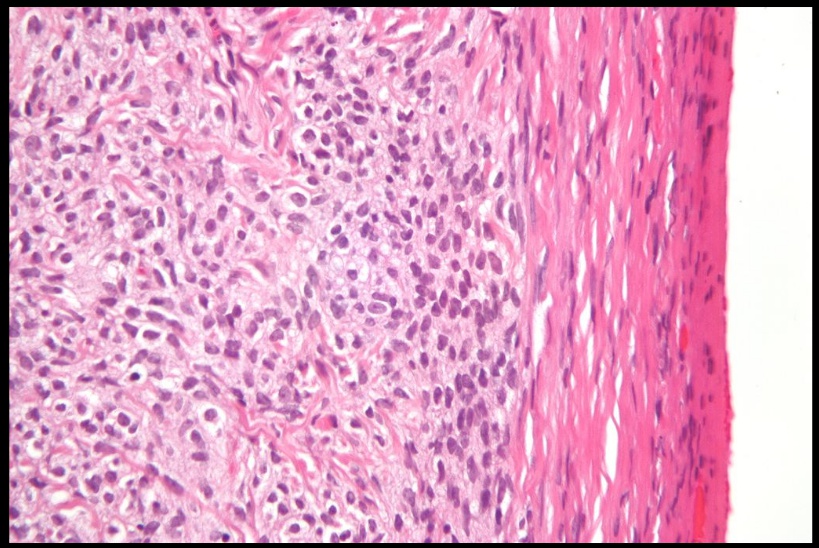

Granulosa cell tumor: showing diffuse proliferation of small round cells.